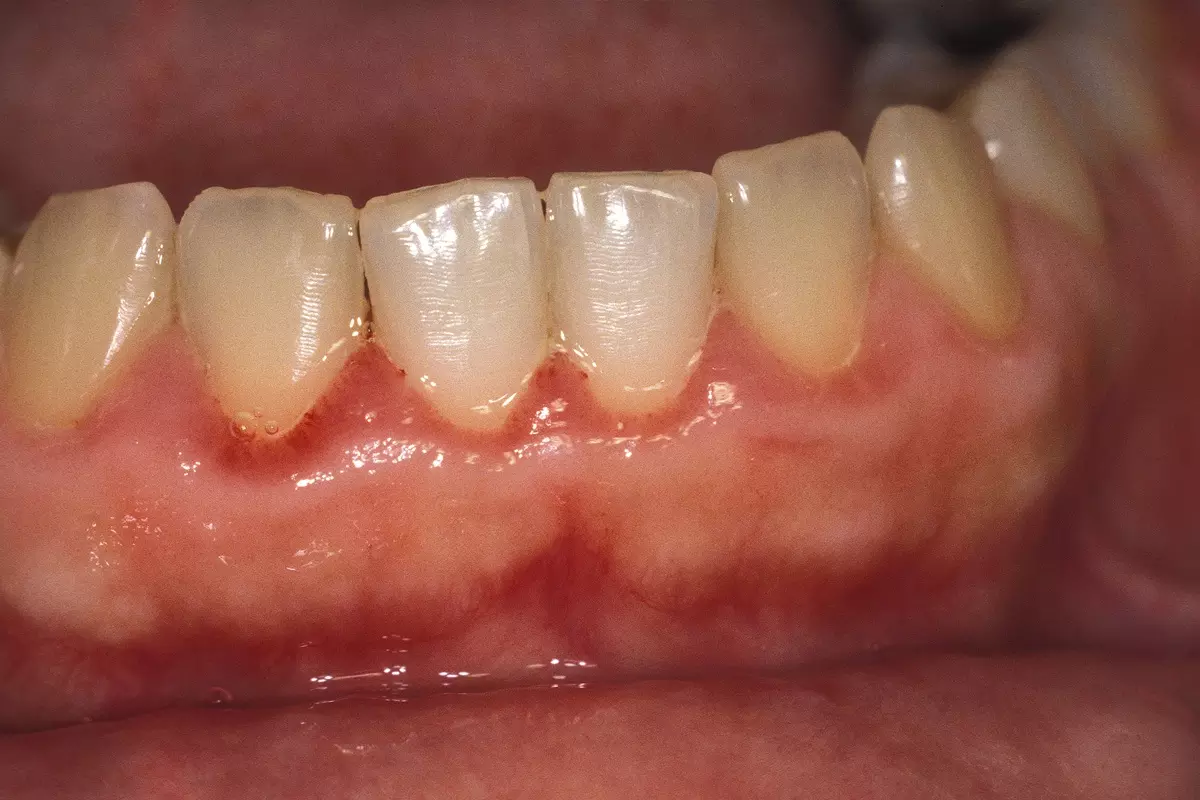

치은염은 잇몸에 염증이 생기는 대표적인 치주 질환이다. 일반적으로는 치태(플라그)나 음식물 찌꺼기 때문에 발생하지만, 임신기나 월경기에는 호르몬 변화로 증상이 더 쉽게, 더 심하게 나타난다. 이 시기에는 에스트로겐과 프로게스테론 분비가 증가하면서 잇몸 조직의 혈류량이 늘어난다. 그 결과 혈관이 확장되고 충혈과 부종이 심해져 염증 반응이 과도하게 나타난다. 잇몸이 선홍색으로 붓고 통증이 생기며, 칫솔질만으로도 쉽게 출혈이 발생하는 것이 특징이다.

월경성 치은염은 보통 월경 1주일 전부터 시작돼 월경이 시작되면 자연스럽게 완화된다. 임신기 치은염은 임신 2~3개월경 나타나 8개월까지 악화하다가, 9개월 이후 점차 호전되는 경향을 보인다.